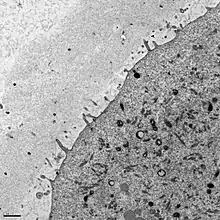

La zone pellucide est une matrice extra-cellulaire glycoprotéique sulfatée qui entoure l’ovocyte. Elle est sécrétée par l’ovocyte I au stade du follicule pré-antral et les cellules péri-ovocytaires de la corona radiata.

Plusieurs types de glycoprotéines sulfatées s’associent pour former un maillage : ZP2 et ZP3 forment des filaments, et ZP1 les relie entre eux. Il existe un 4ème type, les ZP4, mais on n’en connaît pour l’instant pas le rôle[1].

La zone pellucide est essentielle à la survie de l’ovocyte et à la fécondation, elle permet de sélectionner les spermatozoïdes dont la membrane plasmique est intacte et empêche la fécondation croisée (inter espèces). Elle facilite également la migration tubaire de l'ovocyte en évitant une implantation dans les trompes. Chez les mammifères, la glycoprotéine sulfatée ZP3 permet la liaison d'un spermatozoïde sur l'ovocyte de la même espèce ; cette liaison est réversible et déclenche la réaction acrosomiale. À la suite de cette réaction, la membrane interne de l'acrosome se lie de façon irréversible à ZP2. Enfin, des enzymes protéolytiques libérées de l'acrosome assurent une digestion partielle de la zone pellucide permettant aux spermatozoïdes de la traverser. L'action de ces enzymes n'est pas nécessaire et suffisante, le mouvement hyperactivé est quant à lui primordial[réf. souhaitée], les enzymes acrosomiques ne permettent que de rendre plus « facile » la traversée de la zone pellucide grâce au mouvement hyperactivé.